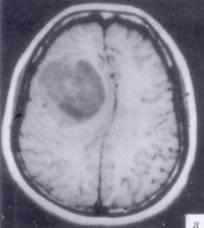

问题 病历摘要:??患者男性,52岁。头痛伴呕吐2月,呕吐呈喷射性。既往身体健康。体检:神清,表情淡漠,反应迟钝,双眼底视神经乳头明显水肿,左鼻唇沟稍浅,左腹壁反射减弱,左上下肢肌力4级,左Babinski征(-)。 下列关于多形性胶质母细胞瘤的叙述哪些是正确的?提示:肿瘤病理报告为多形性胶质母细胞瘤